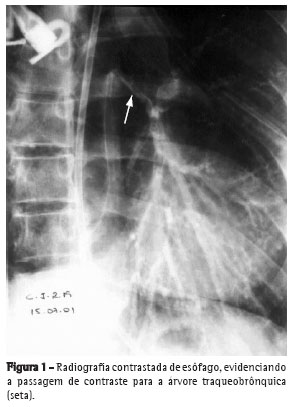

Foi realizada endoscopia digestiva alta, que mostrou a presença de fístula entre o esôfago e brônquio esquerdo, de grandes dimensões, com

passagem do aparelho sem dificuldades (classificação 3b de Zagar(8)). A mucosa esofágica apresentava-se friável com intenso depósito de fibrina. Foi posicionada sonda nasoenteral na segunda porção do duodeno para nutrição (Figura 1).